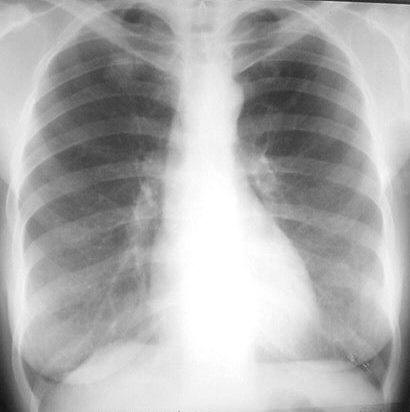

În RM tratamentul bolnavilor de tuberculoză este gratuit, indiferent de faptul dacă persoana este asigurată medical sau nu. Pe parcursul ultimilor ani, în republică se înregistrează o tendinţă de reducere a cazurilor noi de tuberculoză (3807 în anul 2009). Este însă în creştere incidenţa tuberculozei la copii, cu 2,2%, în 2009 fiind înregistrate 235 de cazuri de îmbolnăvire, faţă de 230 în anul 2008. Totodată, este în creştere, cu 6,5%, incidenţa formelor respiratorii.

Riscului de infectare cu tuberculoză sunt supuşi toţi oamenii, indiferent de categorie socială, profesie sau interese, dar riscul de contaminare prin această maladie creşte în condiţiile malnutriţiei, situaţiei sanitare deficitare, suprapopulării, accesului redus la servicii medicale, se spune în comunicatul Ministerului Sănătăţii.

Tuberculoza este a doua cauză infecţioasă de deces în lume, după SIDA, răpind în jur de 3 milioane de vieţi în fiecare an. Potrivit estimărilor, o treime din populaţia lumii este infectată cu bacilul Koch.